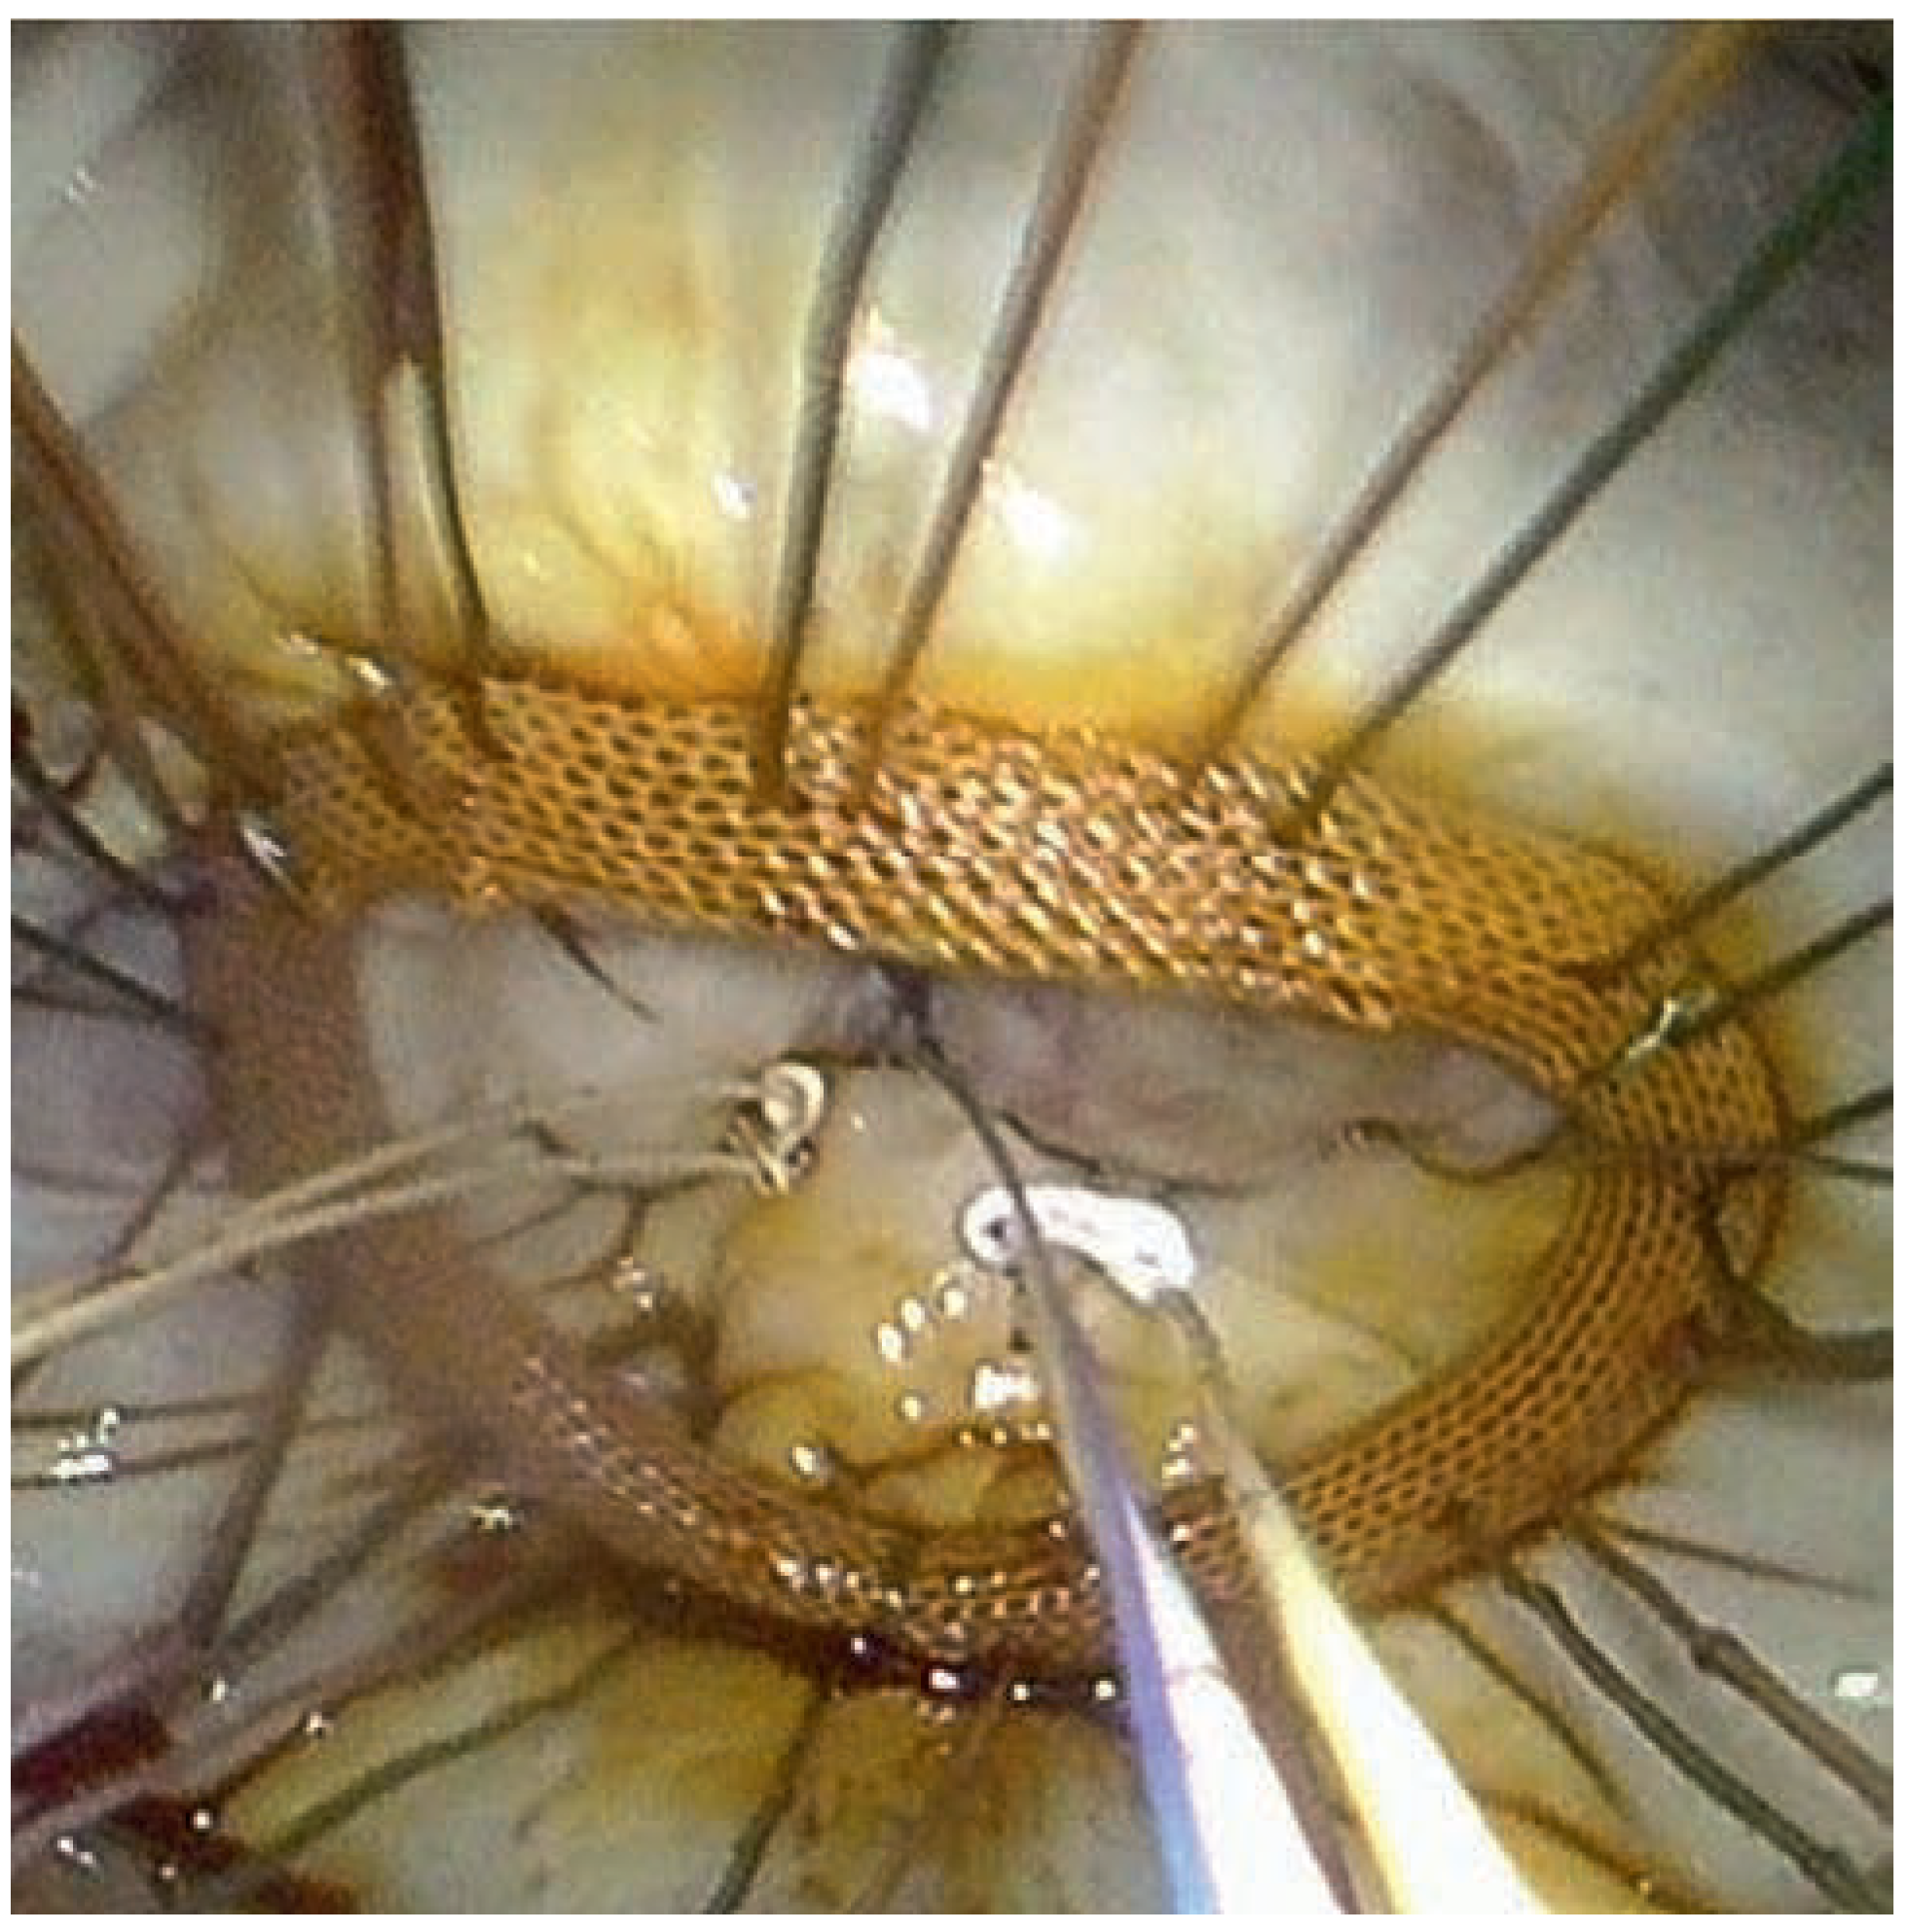

A 59-year-old man was referred to our institution for dyspnea. He had a history of mitral valve regurgitation with posterior leaflet valve prolapse. In 2006 he underwent mitral repair without annuloplasty ring implantation. In April 2012 dyspnea, NYHA II–III, recurred. Echocardiography showed grade III to IV mitral regurgitation. He was referred to another hospital, where percutaneous treatment with MitraClip™ implantation was proposed to the patient. Two MitraClips™ were implanted. Shortly after the intervention the patient complained about shortness of breath. He was seen at our hospital. Transthoracic echocardiography (Figure 1) and cardiac computed tomography (Figure 2) confirmed the clinical impression of both mitral stenosis and regurgitation with significant gradient and a valve surface of 1.7 cm2. M-mode echocardiography showed typical patterns of mitral stenosis (Figure 3). Mitral valve repair with annuloplasty could be performed with neocordals, reinforcement of the posterior leaflet and ring implantation (Figure 4 and Figure 5). Six months later, the mitral valve is fully functional and the patient is asymptomatic. This case is remarkable for a few points: firstly, mitral annuloplasty with ring implantation should be performed instead of simple repair. Secondly, equivalence of surgery with MitraClip™ implantation has been proven in some trials. However patients included in these studies were older and sicker than our patient. There are more arguments to suggest that MitraClip™ should be reserved for nonoperable patients or to patients refusing surgery. In our patient, revision surgery was probably a better option than a percutaneous approach. Valve dysfunction requiring a second intervention is almost 10 times more frequent after MitraClip™ implantation than after conventional surgery. Thirdly, even though trials about MitraClip™ are still ongoing, indications should not be lifted to younger patients, until we have clear evidence regarding the comparison of the 2 techniques. Finally, mitral valve repair with annuloplasty and ring implantation is possible after MitraClip™ implantation.

Figure 4. Perioperative stenosis with mitral valve ballooning. The MitraClip is visible on both leaflets.